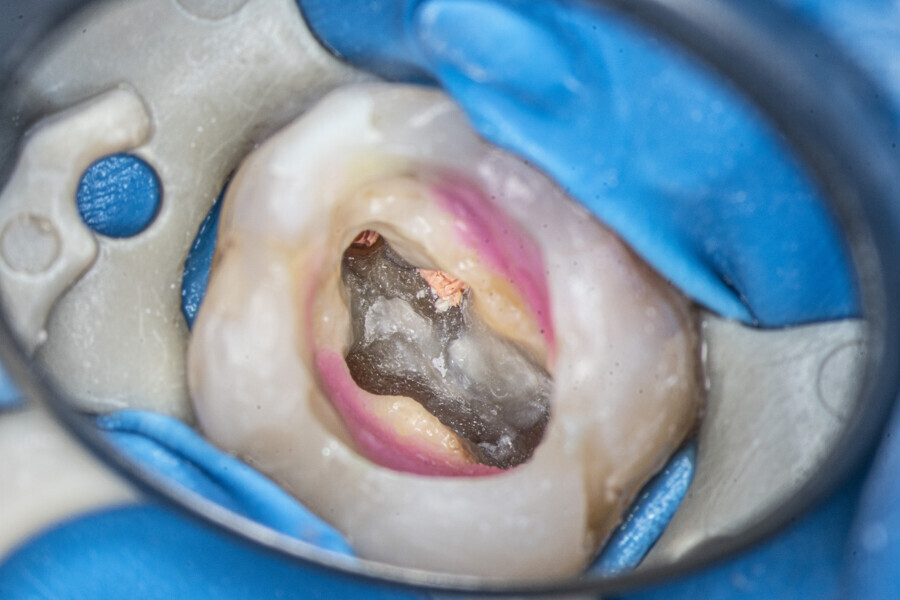

Case 2 (Figs. 27–36)

A 25-year-old female patient presented to the office owing to constant pain related to the mandibular left first molar. Pulp necrosis was diagnosed. After the emergency appointment, the patient was referred for complete treatment. The tooth was treated in the same manner as described in the previous paragraphs. After creation of the access cavity, the orifices were located. In the root chamber, the orifices of the MB, mesiolingual, DB, distomesial and distolingual canals were present. After pre-flaring and preparation of the middle third, the LPE enhanced irrigation protocol with the SkyPulse laser was performed. After the irrigation protocol in the mesial root, the irrigants started to flow between lingual and buccal canals. Such an observation suggested to the operator that some space in the isthmus had been created. It is worth mentioning that at this stage apical enlargement was not performed. Final preparation of all five canals was performed with the reciprocating file, and the final irrigation protocol was performed as in the previous case. The radiograph clearly revealed that the isthmus space was filled with the sealer. The radiograph and CBCT image revealed that there were four portals of exit in the mesial root.